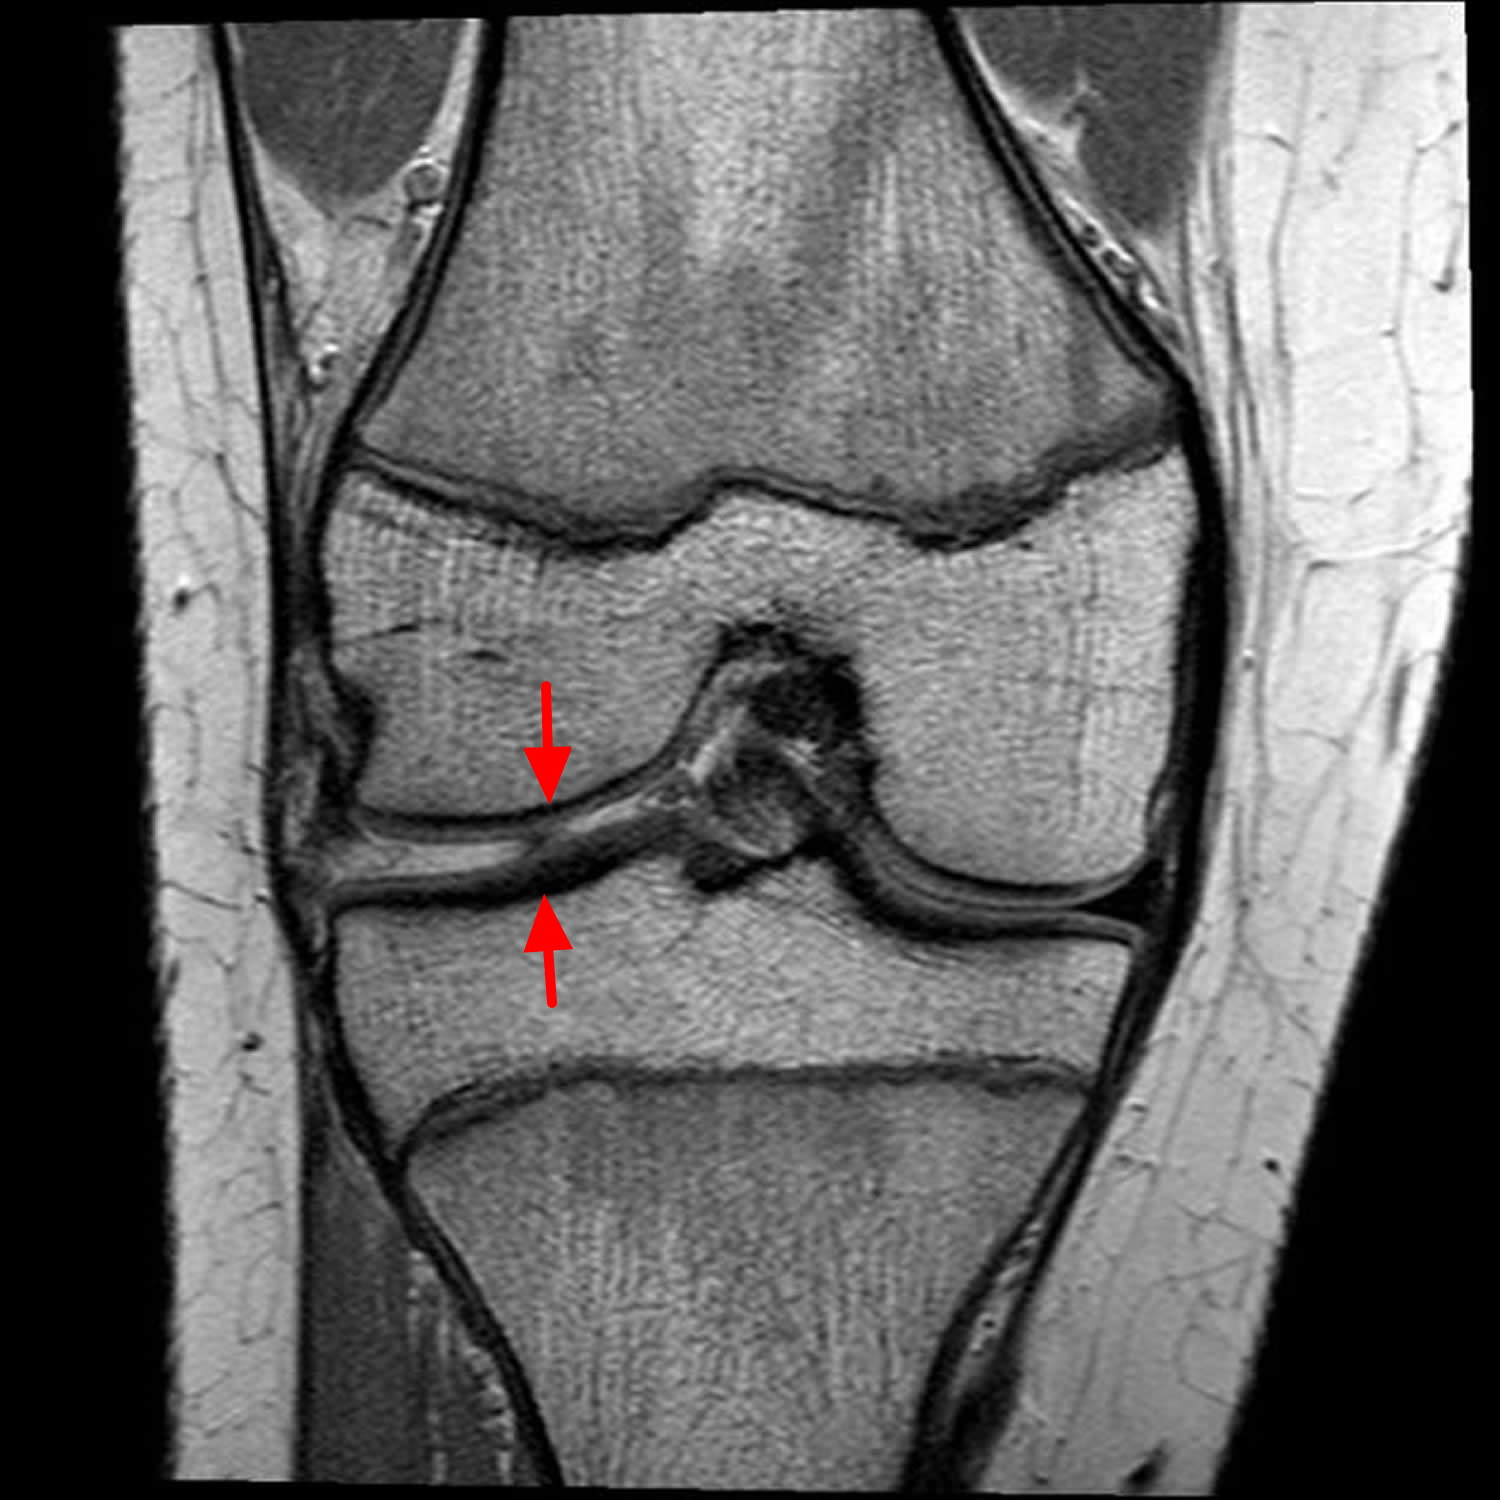

Suffering from a meniscus tear knee injury? Learn the common symptoms, effective treatment options, and essential recovery exercises. Discover expert advice on managing knee pain, exploring non-surgical physical therapy, and knowing when surgery is necessary to restore joint mobility and return to your daily activities safely. Get the facts you need for a faster, pain-free recovery today.